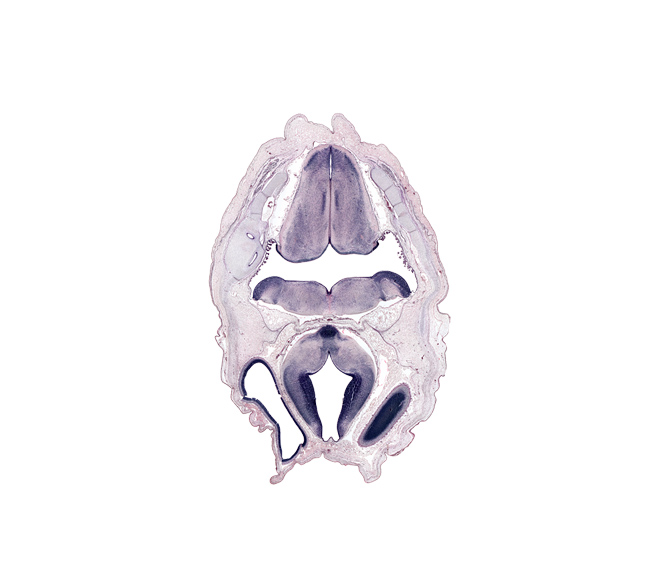

Boyd Embryo #H983 | Location: 39-1-4

Keywords: choroid plexus, dural limiting membrane, edge of cerebral vesicle (hemisphere), exoccipital, head mesenchyme, junction of diencephalon and mesencephalon, mamillary region, medial accessory olivary nucleus, median sulcus, oculomotor nerve (CN III), osteogenic layer, otic capsule, posterior cerebral artery, posterior dural venous plexus, roof plate of diencephalon, surface ectoderm, tractus solitarius nucleus

Source: The Virtual Human Embryo.